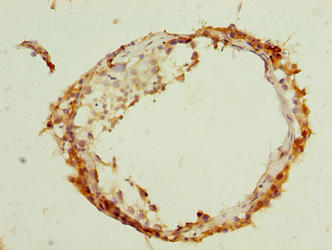

Immunohistochemistry of paraffin-embedded human liver cancer using CSB-PA755485LA01HU at dilution of 1:100

Immunohistochemistry of paraffin-embedded human testis tissue using CSB-PA755485LA01HU at dilution of 1:100